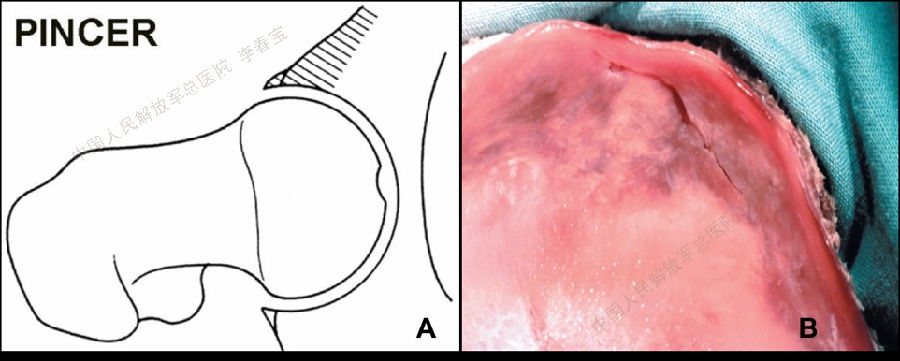

2. 髋关节撞击症

髋关节撞击征(femoroacetabular impingement, FAI)是引起中青年,特别是运动量较大者髋关节疼痛的主要原因,也是引起早期骨关节炎的重要因素。按受累解剖部位形态学改变,FAI 可分为:(1)凸轮型撞击(cam impingement);(2)钳夹型撞击(pincer impingement);(3)凸轮钳夹混合型撞击(mixed type)。该病好发于喜欢运动的青壮年,患者常有不明原因的髋关节慢性疼痛,以腹股沟区最为多见,也可出现股骨后侧和外侧疼痛,同时伴有髋关节活动受限,以屈曲内旋受限最为显著。通过髋部X片(包括骨盆正位X线片、髋关节穿桌侧位、蛙式侧位X线片、屈髋侧位片或假斜位片)、MRI和CT检查一般不难诊断。一般经休息、限制髋关节运动、服用非甾体抗炎药以及封闭治疗等保守治疗无效可考虑手术治疗。治疗方面,早期主要是通过股骨头脱位技术进行开放手术治疗,目前的主流是通过髋关节镜微创技术进行治疗,包括镜下清理凸轮畸形,恢复股骨头颈区的自然弧度;清除髋臼边缘的骨赘和适当磨除髋臼周围影响髋关节活动的骨质,以减少髋臼前方的过度覆盖,最后把髋臼盂唇剩余部分缝合固定在骨面或髋臼缘上。